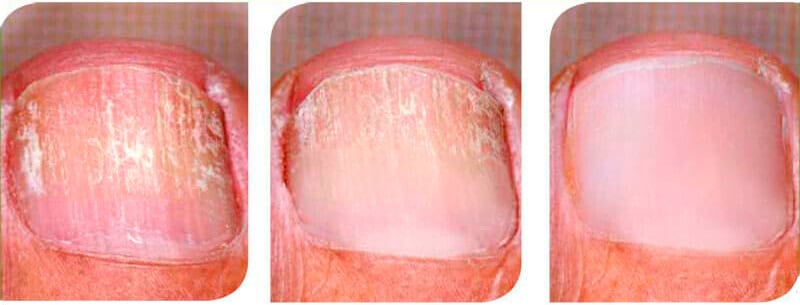

კლინიკაში პროფესორი კირა სარალიძე მიმყვა. ჩემი მკურნალობა დაახლოებით ექვსი თვე გაგრძელდა. ვინაიდან ღვიძლიც დამემართა, წამლები და სხვა ნატურალური პროდუქტები მომცეს, ფეხებს კი Clareon კრემით ვუმკურნალე. ერთი თვის შემდეგ, როცა ჩემს ღვიძლს საფრთხე აღარ ემუქრებოდა, მხოლოდ კრემი გამოვიყენე. ახლა კი შედეგებს გაგიზიარებთ, რადგან ძალიან მიხარია, რომ ოპერაციის გარეშე მოვახერხე ფეხის მიკოზის დაძლევა.

ამ კრემს დღეში 2-ჯერ ვიყენებდი და მთელი პროცესი გადავიღე. 2 თვის შემდეგ ფრჩხილი უკვე ნორმალურად გამოიყურებოდა. Ძალიან ბედნიერი ვარ.

ჩემი ქმარი 3 წლის განმავლობაში იტანჯებოდა საფუარის ინფექციით და ეს იყო აბსოლუტური კოშმარი. მისი ფრჩხილები ძალიან ყვითელი იყო და საშინელი სუნი ჰქონდა. რამდენიმე ნარკოტიკი გამოვიყენეთ. ზუსტი სახელები არ მახსოვს, მაგრამ არ დამეხმარნენ. დანებებას აპირებდა, მაგრამ მერე მეგობარმა „Clareon“ ურჩია. შეხედეთ შედეგებს მხოლოდ ერთი კვირის შემდეგ.